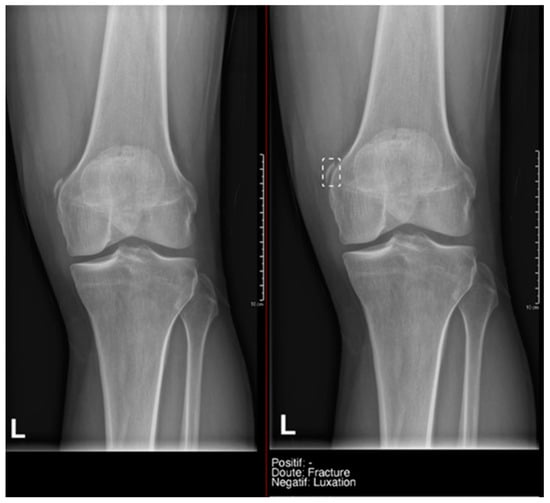

- Ankle and foot: On six occasions, Milvue marked the fracture variable as doubtful in cases with a bipartite medial sesamoid (two patients), an accessory sesamoid at the base of the 5th metatarsal, synphalangism, os peroneum, and os naviculare. (Figure 8).

- Hand: Milvue marked the fracture variable as doubtful in the case of multiple accessory ossicles.

- Wrist: On four occasions, Milvue marked the fracture variable as doubtful in cases of os paranaviculare, os trapezium secundarium, os ulnar styloid, and os paratrapezium. However, Milvue did not detect fractures in three cases of os ulnar styloid, two cases of accessory ulnar styloid, nor in cases of os hypolunatum and os epilunatum.